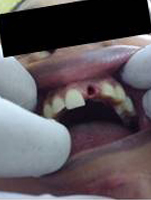

Pre Operation

Single Tooth Implant

Placement of Bone Grafting